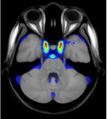

A statistical atlas of cerebral arteries

Magnetic resonance angiography (MRA) can capture the variation of cerebral arteries with high spatial resolution. These measurements include valuable information about the morphology, geometry, and density of brain arteries, which may be useful to identify risk factors for cerebrovascular and neurological diseases at an early time point. However, this requires knowledge about the distribution and morphology of vessels in healthy subjects. the statistical arterial brain atlas described in this work is a free and public neuroimaging resource that can be used to identify vascular morphological changes. The atlas was generated based on 544 freely available multi-center MRA and T1-weighted MRI datasets. the arteries were automatically segmented in each MRA dataset and used for vessel radius quantification. The binary segmentation and vessel size information were non-linearly registered to the MNI brain atlas using the T1-weighted MRI datasets to construct atlases of artery occurrence probability, mean artery radius, and artery radius standard deviation. This public neuroimaging resource improves the understanding of the distribution and size of arteries in the healthy human brain.

The statistical atlas consists of four image files in the niftii format and in MNI reference space (0.5 mm^3). These files include the TOF MRA average atlas (tofAverage.nii.gz), the vessel probability atlas (vesselProbabilities.nii.gz [in %]), the mean artery radius atlas (vesselRadius.nii.gz [in mm]), and the standard deviation of the artery radius atlas (vesselRadiusStd.nii.gz [in mm]). All images are saved using float values. The TOF MRA and T1-weighted datasets used for atlas generation can be downloaded from the original sources.